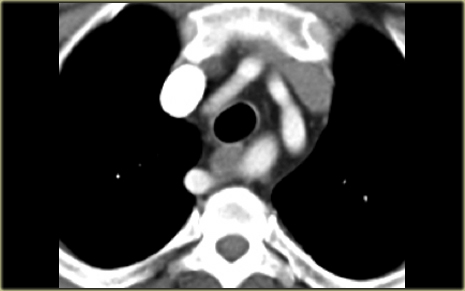

Right Arch with Aberrant left subclavian

The Right Aortic Arch with an aberrant left subclavian is an obstructing arch anomaly.

The first branch of the aorta is the left common carotid, followed by the right subclavian artery and the left common carotid.

This also is a true ring.

The ligamentum ductus arteriosus between the arch at the level of the left subclavian artery and the left pumonary artery completes the ring.

If this ligament is very short, there will be a lot of compression.

On the left a patient with a right arch with an aberrant left subclavian (indicated by the yellow arrow).

There is a right arch and the left subclavian artery is the last branch of the aortic arch, indicating that this is an aberrant left subclavian.

Medially to the left subclavian artery we see the left common carotid, that originates from the right side and has an oblique course to the left.

The yellow arrow indicates the azygos vein.

The green arrow indicates the left superior intercostal vein, a normal variant, that we will discuss later.